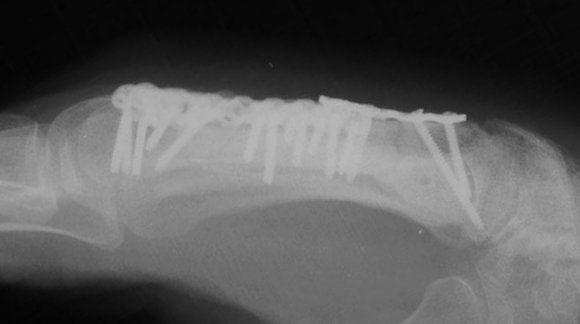

I used the Synthes modular hand set, which has screw intervals different than the small fragment set.

Click for larger image

This was the longest plate available, not optimum, but had six cortex purchase on each side of the graft.